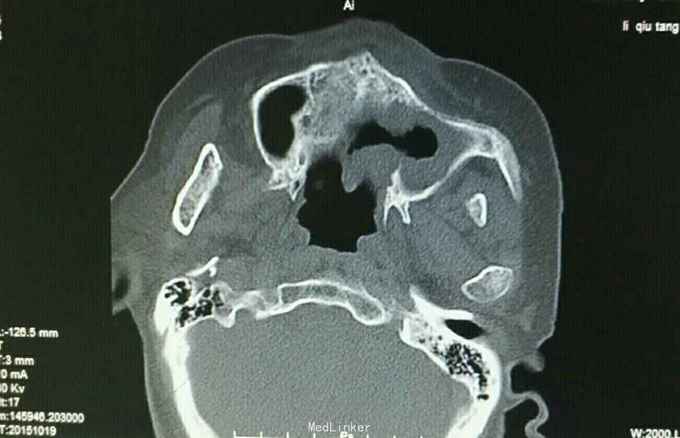

诊断:左上牙龈癌术后复发 治疗:2015.10.21CT引导下行碘125粒子植入术,图为术前定位

肿瘤的治疗应该多元化,该患者属于牙龈癌术后复发,患者不接受放化疗,遂予以碘125粒子植入术,手术成功,嘱患者术后45天返院复诊。